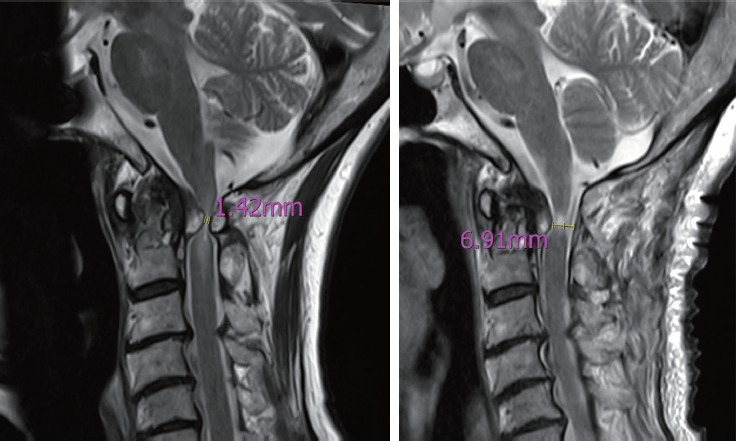

Results: Among 112 patients, 57 (50.9%) had ROP. The ROP-positive group was older (67.37±13.13 years vs. 56.90±15.15 years, p<0.001) and had lower ADI (5.63±2.77 mm vs. 6.99±2.33 mm, p=0.034), ΔADI (3.01±2.27 mm vs. 3.89±2.07 mm, p=0.006), and C2-7 ROM (30.78°±15.45° vs. 41.73°±16.58°, p<0.001). In ROP subgroups, the cystic group had greater C1-2 ROM (15.69°±6.34° vs. 10.00°±7.72°, p=0.013) and ADI (6.98±2.68 mm vs. 5.14±2.66 mm, p=0.042). Immediate postoperative ROP thickness remained greater in the cystic group (6.85±2.49 vs. 5.21±1.82 mm, p=0.042), while ROP thickness at 3 months and 1 year showed no significant differences. JOA recovery rates were similar.